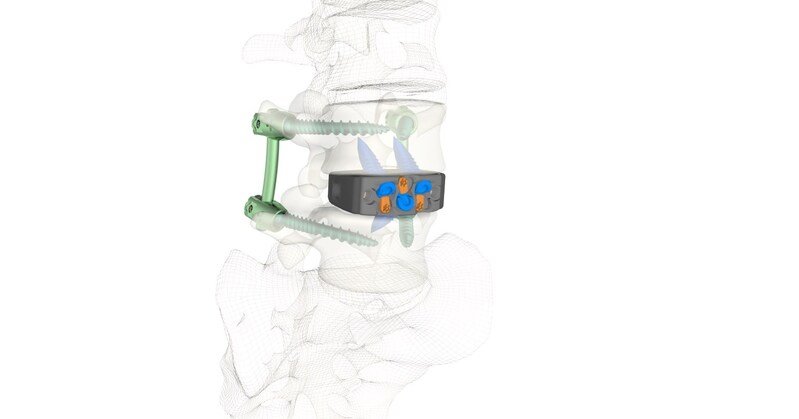

FLOWOOD, Miss., Nov. 15, 2025 /PRNewswire/ — Zavation Medical Products, LLC (“Zavation”), a leading innovator in spinal device technology, announces the first successful implantations of the Varisync® ALIF NanoPrime™ System, a next-generation stand-alone ALIF system featuring Zavation’s proprietary titanium ion bond technology.

NanoPrime™ combines the mechanical advantages of PEEK with the biological benefits of titanium, providing enhanced radiographic visualization, biomechanical compatibility5, and fusion potential1, 2, 3, 4.

“The NanoPrime™ ALIF cage offered excellent radiographic visibility and the potential to lead to positive surgical outcomes,” said Dr. Steve Zhou. “Its softer modulus compared to pure titanium reduces the risk of subsidence, while the titanium-bonded surface promotes solid fusion and eliminates my concerns of fibrous union.”

Lane Major, Chief Executive Officer of Zavation, said, “Varisync® ALIF NanoPrime™ reflects our commitment to bringing truly differentiated technology to spine surgery. This system combines thoughtful design with advanced material science, giving surgeons a streamlined and versatile option in the anterior space. It is the kind of innovation that reinforces our mission to elevate patient care and support the clinical needs of our partners.”